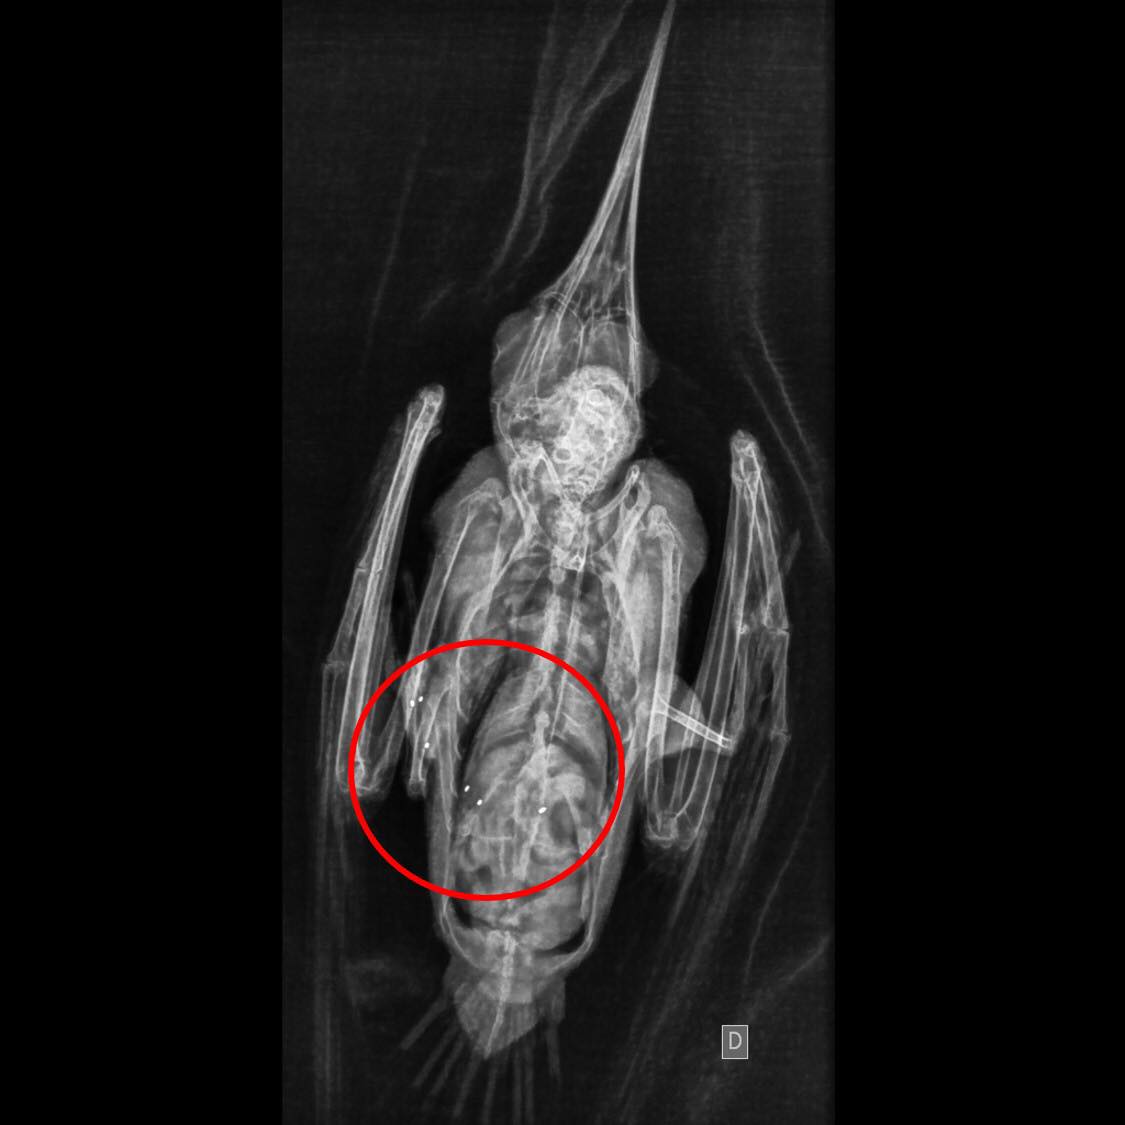

A médica veterinária Raquel Beneton Ferioli, explicou que a colocação de implantes de ouro em seis acupontos foi necessária para recuperar uma lesão articular no membro inferior esquerdo do trinta-réis.